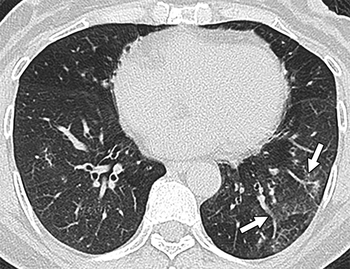

A team of international experts published seven recommendations for the use of chest imaging in the diagnosis and management of COVID-19-positive patients.

Images demonstrate high accuracy for identifying B-lines, thickened pleural lines, and pulmonary consolidation features.